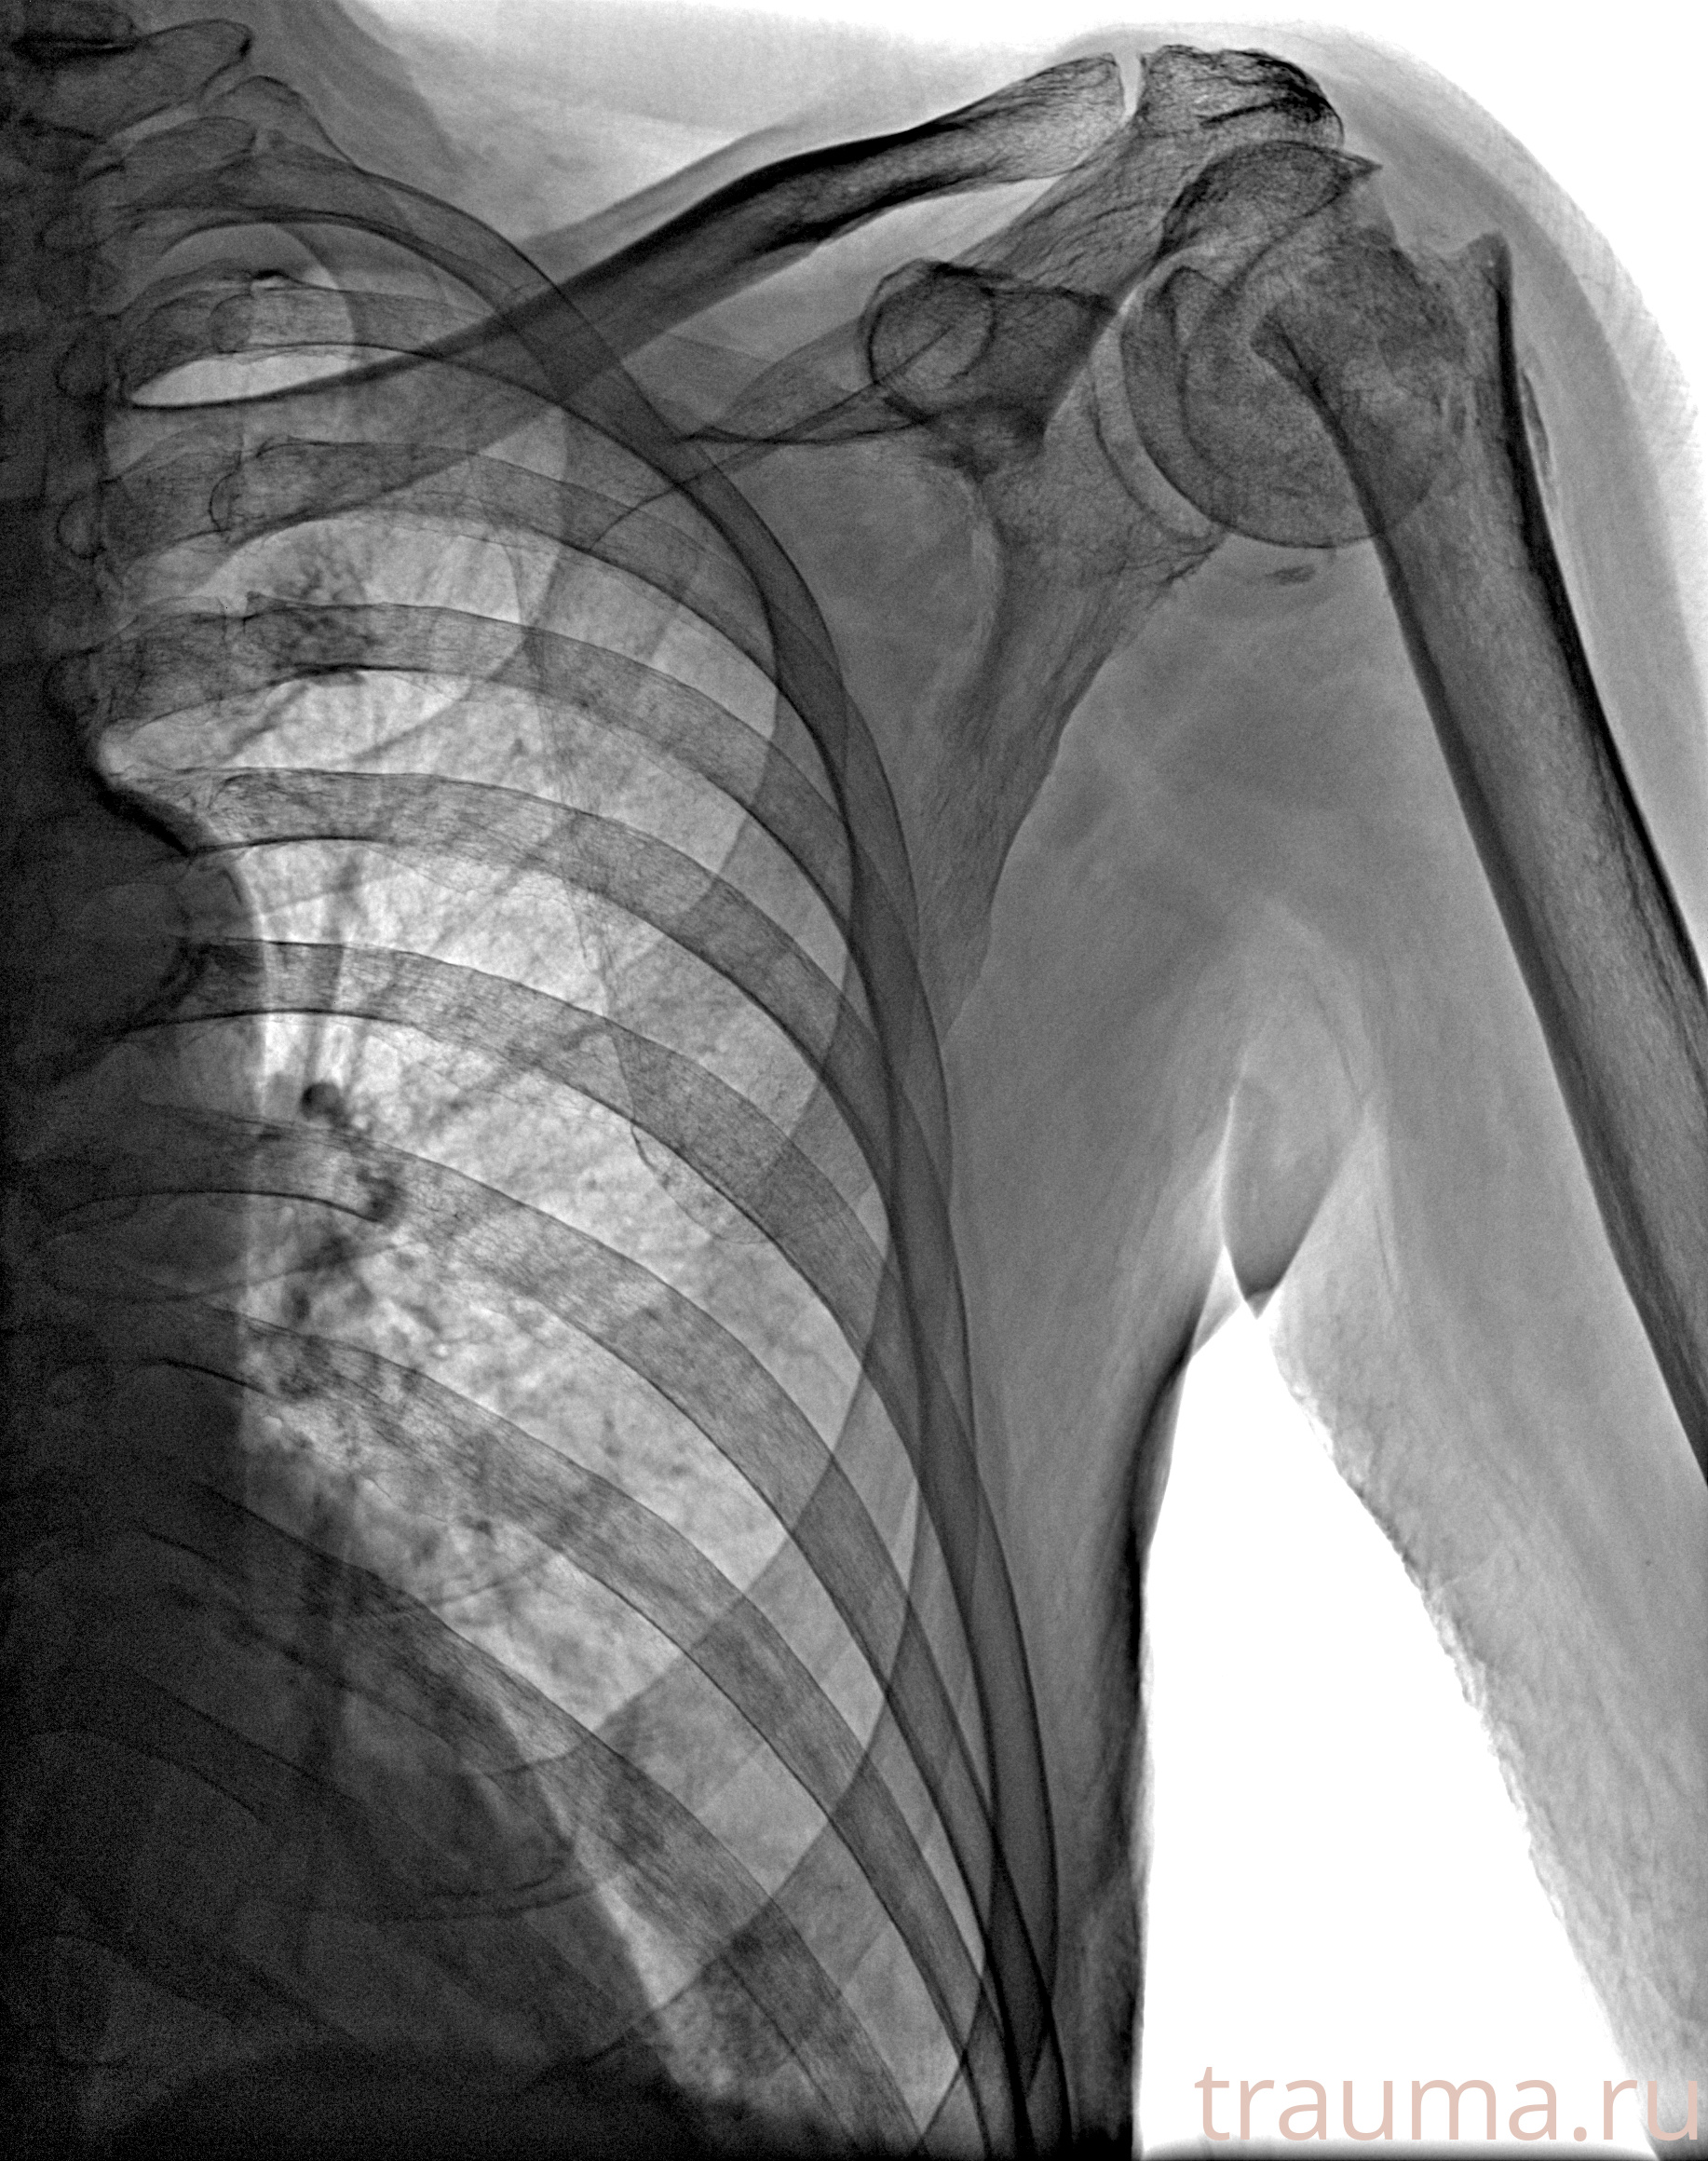

Рентгенограммы

Рентген на дому: по вашему адресу приезжает врач-рентгенолог, травматолог-ортопед с мобильным рентгеновским аппаратом, проводит диагностику травмы или заболевания, делает необходимые рентгенограммы, дает рекомендации по дальнейшему лечению. Получить качественные снимки в домашних условиях возможно благодаря уникальной методике, разработанной МосРентген Центром для института  Склифосовского